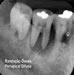

| Lesões do Periápice e Periodonto |

Lesões do Periápice e Periodonto